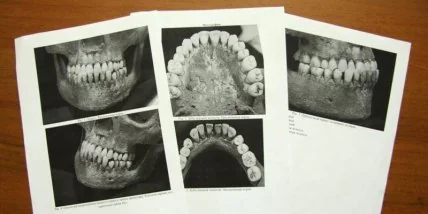

В частности, краниотригонометрические исследования выявили сходство 22 формообразующих параметров в мозговой коробке, а также лицевом скелете с таковыми же у Татьяны. По результатам остеологии, краниологии, остеокопии, одонтологии и палеопатологическому анализу большинство ученых с максимальной долей уверенности считают, что в Чебоксарах обнаружено именно захоронение Марии Шестовой.